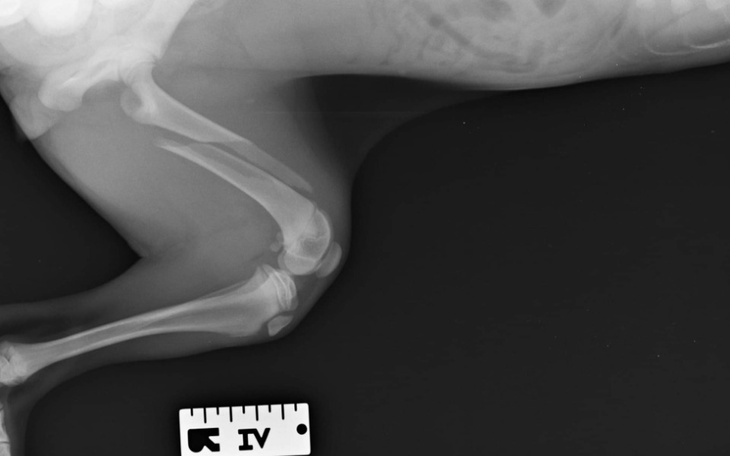

Proszę o pomoc 😪w ostatnim czasie przygarnęłam dwie suczki - szczenięta. Niestety jedno z nich dostało urazu nóżki, prawdopodobnie po kontakcie z drugim psem od sąsiadów. Przesliznęlo się przez dziurę w płocie. Jak się okazało po wizycie weterynaryjnej złamanie kości udowej spiralne. Po konsultacji w Klinice Weterynarii we Wrocławiu wyceniono operacje i koszty leczenia na około 3000 tyś złotych. Niestety nie stać mnie na taki wydatek . Bardzo proszę o pomoc ludzi z dobrymi serduszkami. W załączeniu przedstawiam potwierdzenie wizyty u weterynarza, zdjęcie rtg oraz zdjęcie suni. Po operacji przedstawię również rachunek za operacje oraz inne wydatki takie jak np leki. Bardzo proszę o pomoc .